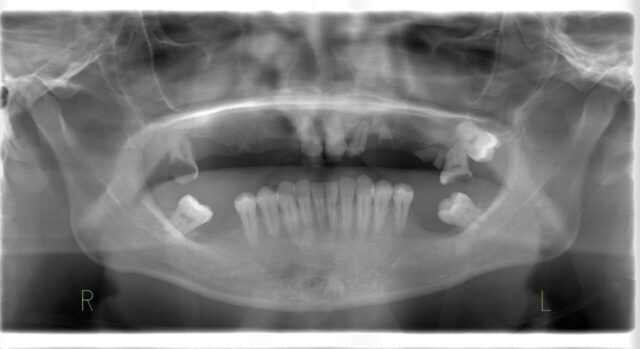

BEFORE

術前